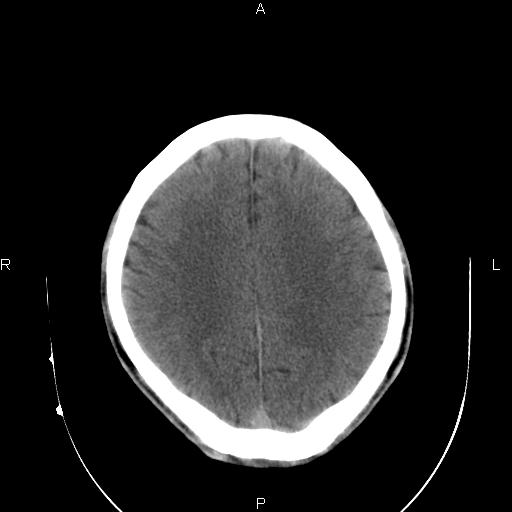

男性,40岁,反复头痛,视物旋转一月余,无呕吐,pe未见明确异常。

我的问题是上矢状窦高密度怎么解释?请各位专家不吝指教,谢谢!

可结合增强或mrv检查除外上矢状窦血栓。